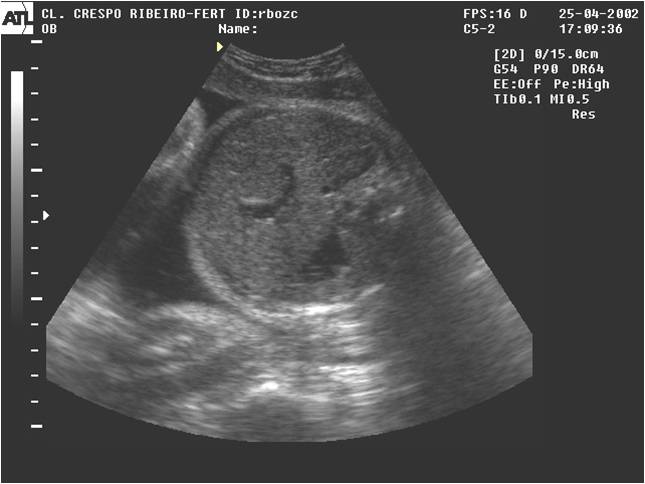

Como dá para saber quanto líquido tem dentro da barriga?

Para medir a quantidade de líquido, é preciso fazer um ultra-som. Seu médico vai solicitar um se desconfiar de que a quantidade de líquido está abaixo da ideal. Veja alguns sinais de que isso pode estar ocorrendo:• quando a mulher está perdendo líquido amniótico pela vagina

Com a ultra-sonografia, dá para medir os bolsões de líquido em vários pontos do útero (o espaço entre o bebê e a parede uterina), e o especialista faz um cálculo que resulta no índice de líquido amniótico (ILA). No terceiro trimestre, o ILA deve estar entre 5 cm e 25 cm. Um índice abaixo de 7 cm é considerado sinal de alerta, e com menos de 5 cm pode fazer com que os médicos prefiram adiantar o parto.

Índice de Líquido Amniótico

|

| Moore &Cayle,1990 |

Poli-hidrâmnio relativo ILA= 250-300mm

Poli-hidrâmnio absoluto ILA> 300 mm

Oligo-hidrâmnio relativo ILA= 20-80 mm

Oligo-hidrâmnio absoluto ILA< 20 mm